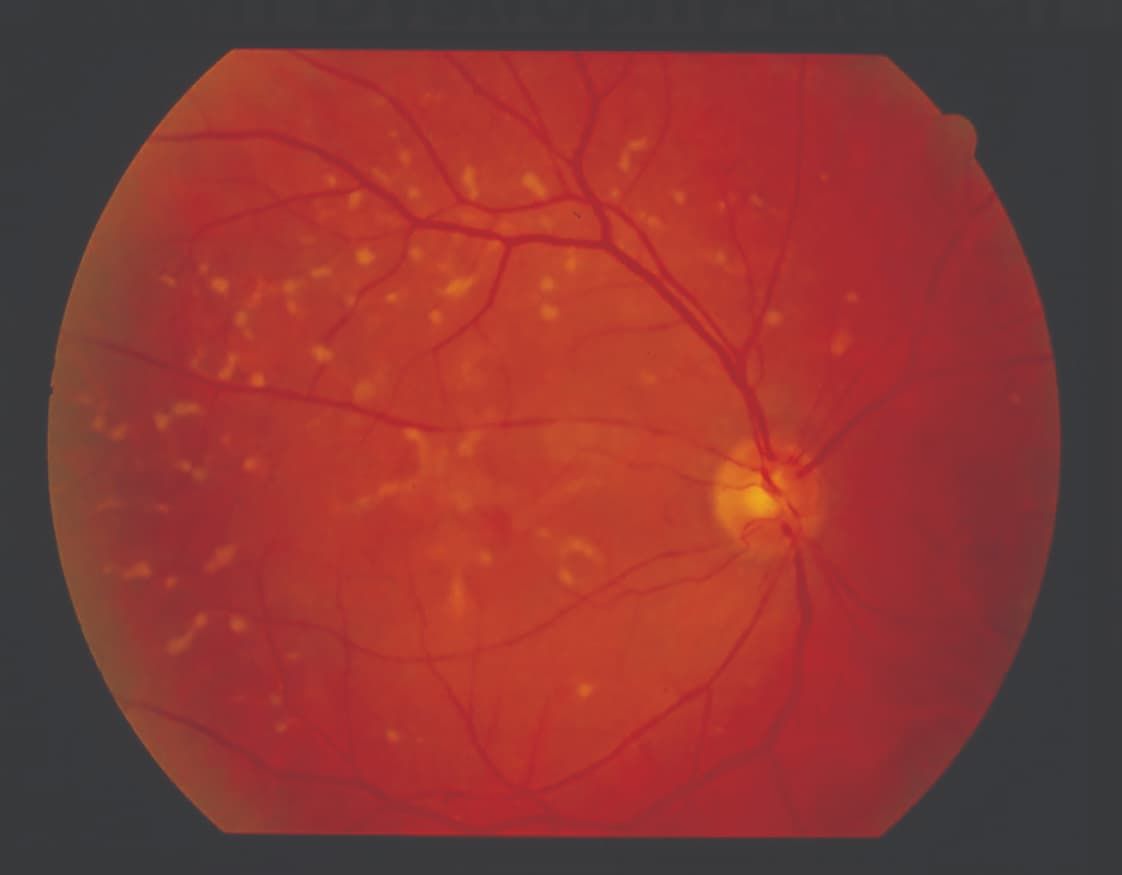

Fundus autofluorescence (FAF) allows visualization of the typical hallmark hyperautofluorescence pattern along the border of a GA lesion. The technique uses the natural fluorescence of lipofuscin in the retinal pigment epithelium (RPE) and can also help in differentiating IRDs, particularly by identifying RPE changes and atrophy (Figure 1).

Figure 1 (top): A blue fundus autofluorescence image of the left eye of a woman aged 86 years with a multifocal pattern of geographic atrophy with perilesional hyperautofluorescence.